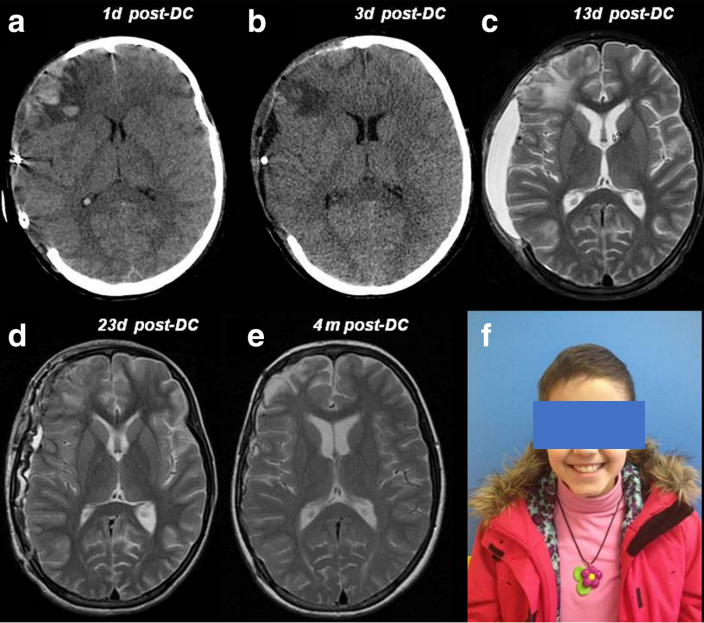

INC国际儿童脑瘤大咖、世界小儿神经系统知名杂志 《Childs Nervous System》现任主编 Concezio Di Rocco教授 发表研究《Problems of reconstructive cranioplasty after traumatic brain injury in children》(儿童创伤性脑损伤...